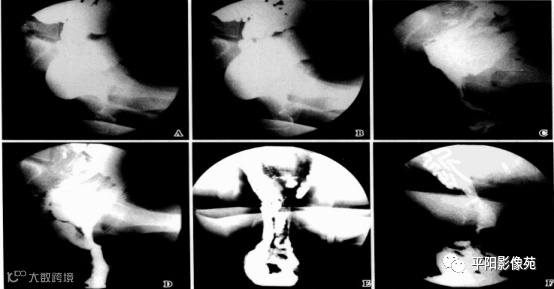

直肠外脱垂(external rectal prolapse,ERP):也成直肠脱垂或完全性直肠脱垂,即直肠脱垂于肛门外,形成大小不等、长短不一和形状不同的肛门外脱垂物块。有时可见小肠参与脱垂。(图4)

图4 A.静坐相;B提肛相,无异常;C.初排相;D~F.力排正侧位相均显示直肠脱出于肛门外,并见小肠参与一起脱出。